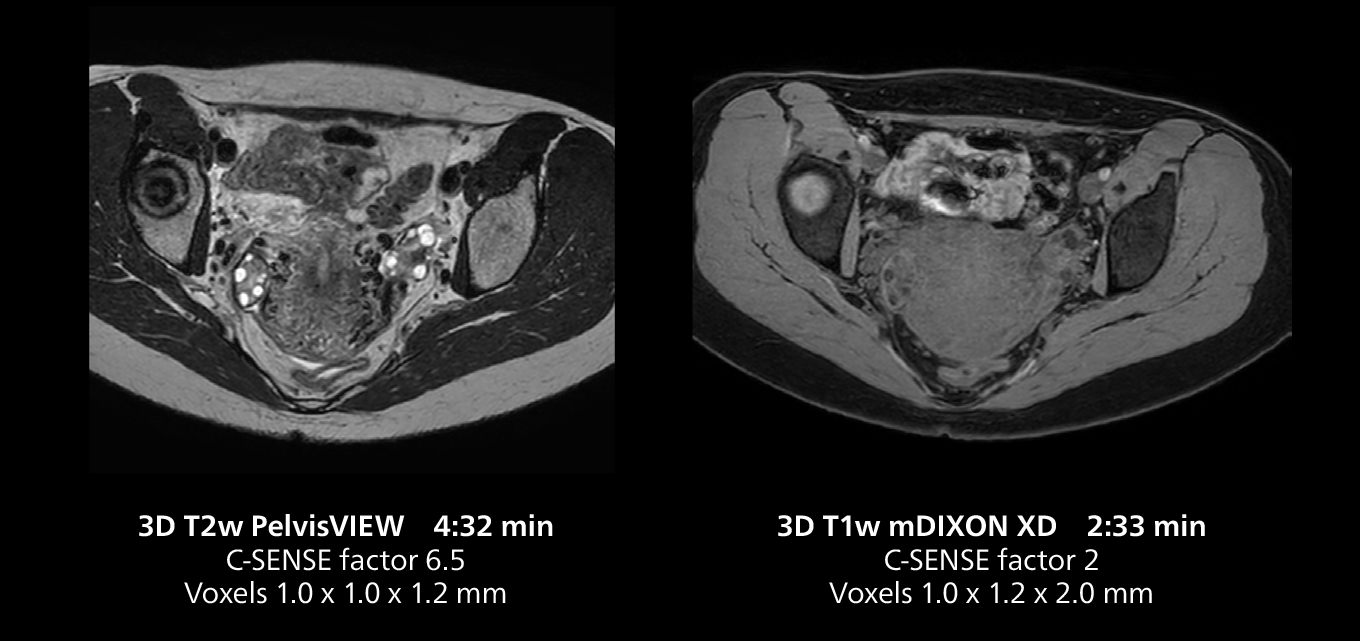

The isotropic high resolution 3D sequence in this MRI case allows for reformatting to obtain other orientations with high quality. Acquired on the MR 5300 system.

The MR 5300 with Compressed SENSE is up to 50%** faster for many exams. It can provide routine exams in less than 5 minutes and whole-body exams in less than 20 minutes. Saint-Augustin has taken advantage of that speed to create highly efficient protocols. The hospital’s standard stroke protocol is just about 8 minutes, and standard ENT, prostate PIRADS staging, and endometriosis studies all clock in at just about 10 minutes.***

“We have more speed in 3D sequences,” Dr. Gellée states. “With Compressed SENSE, we can replace two or three 2D scans withone high-quality 3D scan. High quality additional orientations are then obtained by post-processing of the 3D data set, thus saving scanning time.”